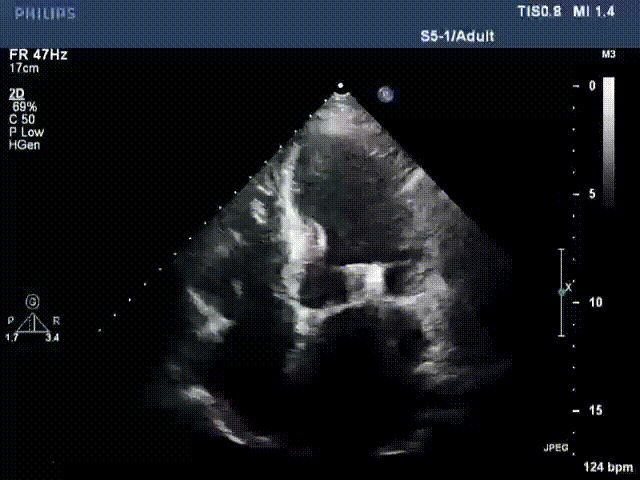

術(shù)前超聲提示二尖瓣重度反流

術(shù)后超聲顯示二尖瓣反流消失,瓣膜夾穩(wěn)定

接受治療的是一例器質(zhì)性重度二尖瓣反流(DMR)患者,主訴“反復(fù)活動后胸悶,氣促3年余”。術(shù)前超聲顯示,雙房增大,二尖瓣脫垂伴重度反流,輕度三尖瓣反流,輕度肺高壓,升主動脈增寬。手術(shù)經(jīng)股靜脈-房間隔入路,采用全身麻醉插管,在TEE和DSA引導(dǎo)下完成房間隔穿刺。置入JensClip瓣膜夾系統(tǒng)后,在左房調(diào)整瓣膜夾的位置和軸向,后進(jìn)入左室,在TEE引導(dǎo)下捕捉二尖瓣前后瓣葉,并關(guān)閉瓣膜夾。經(jīng)TEE反復(fù)確認(rèn)手術(shù)效果后最終鎖定并釋放瓣膜夾。術(shù)后即刻超聲顯示瓣膜夾位置穩(wěn)定,功能良好,術(shù)前二尖瓣反流4+,術(shù)后0反流,肺靜脈逆流和左房壓都顯著好轉(zhuǎn),手術(shù)圓滿成功(以上數(shù)據(jù)都來源于醫(yī)院的臨床記錄)。術(shù)后患者狀態(tài)良好,目前已安排出院。